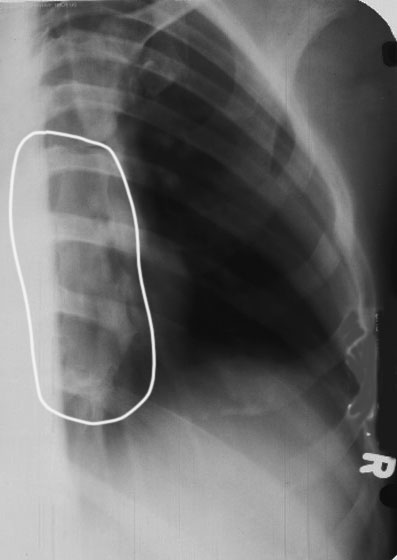

What does over-rotation look like in RAO sternum?

Sternum lateral to heart shadow, foreshortened.